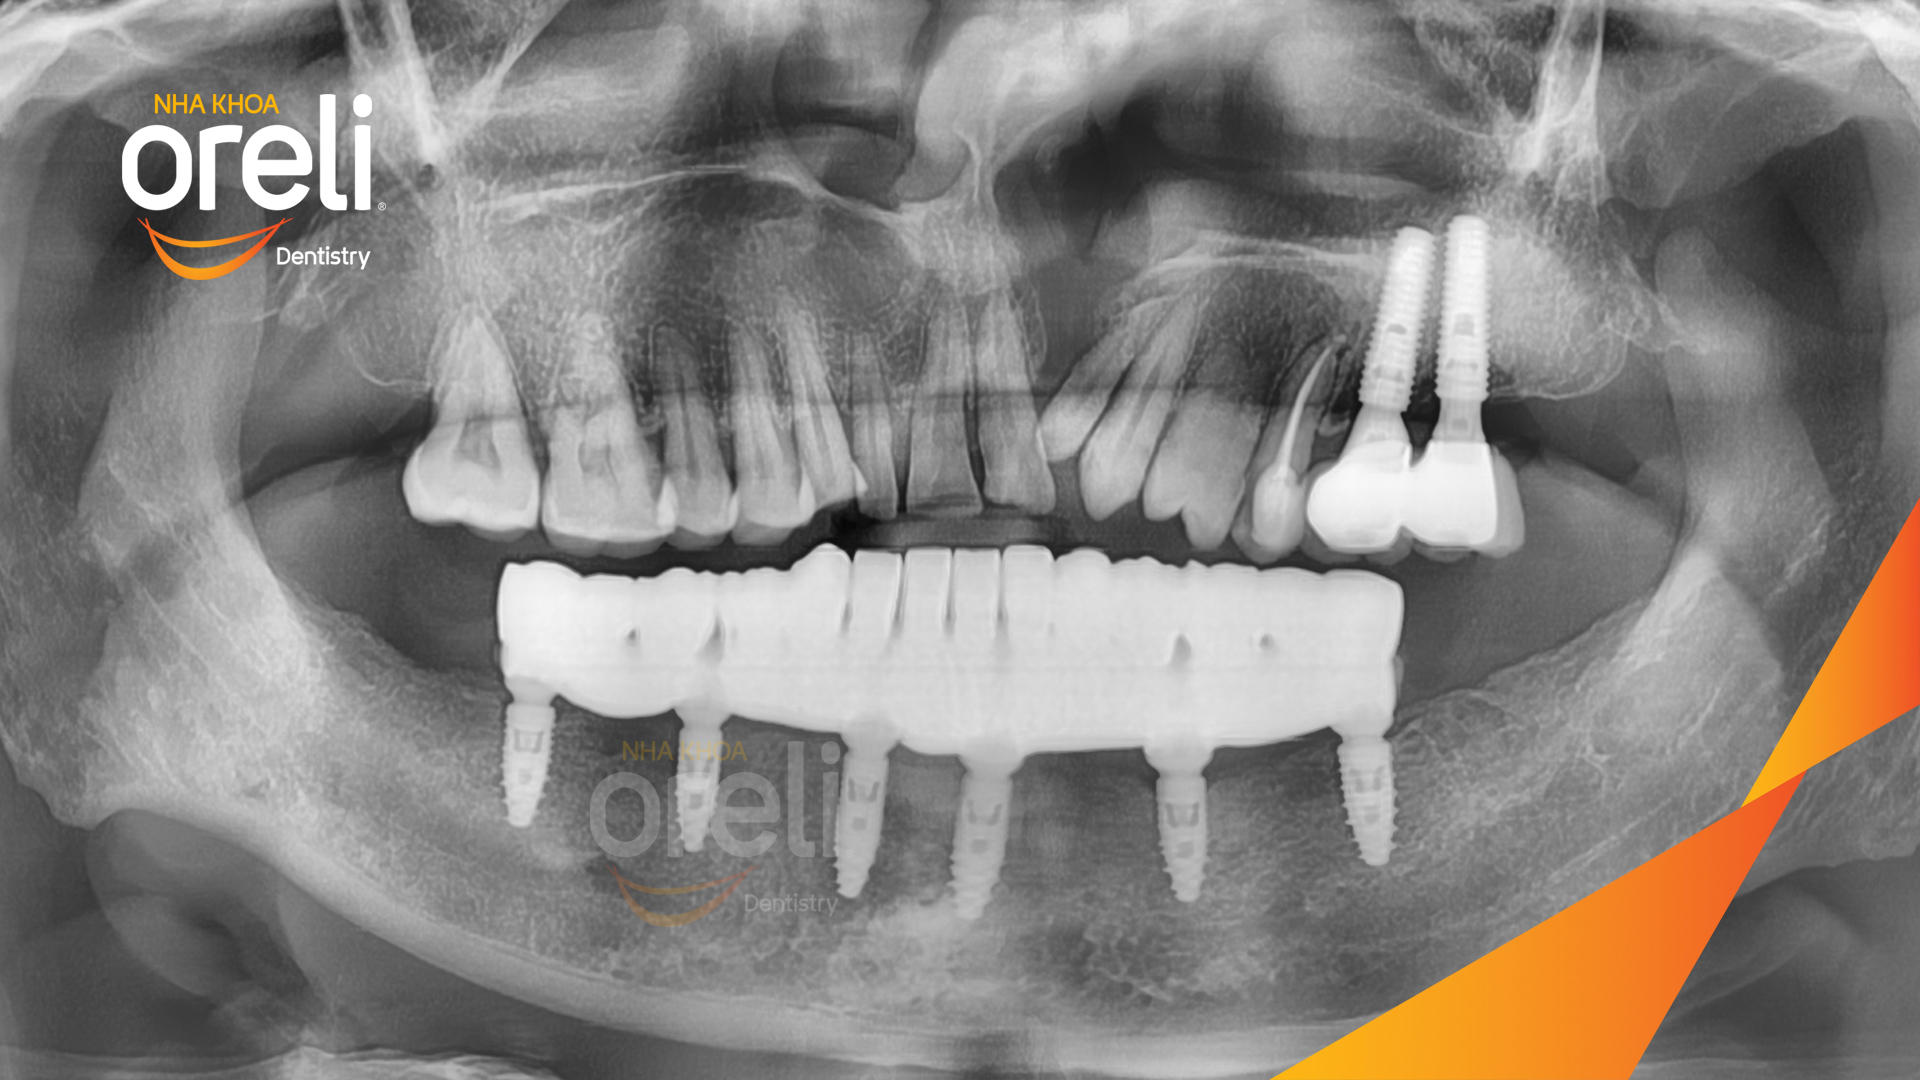

Giải pháp: Nhổ răng trồng răng implant hàm dưới và hai răng hàm trên

Kết quả: Phục hồi vững chắc hàm dưới